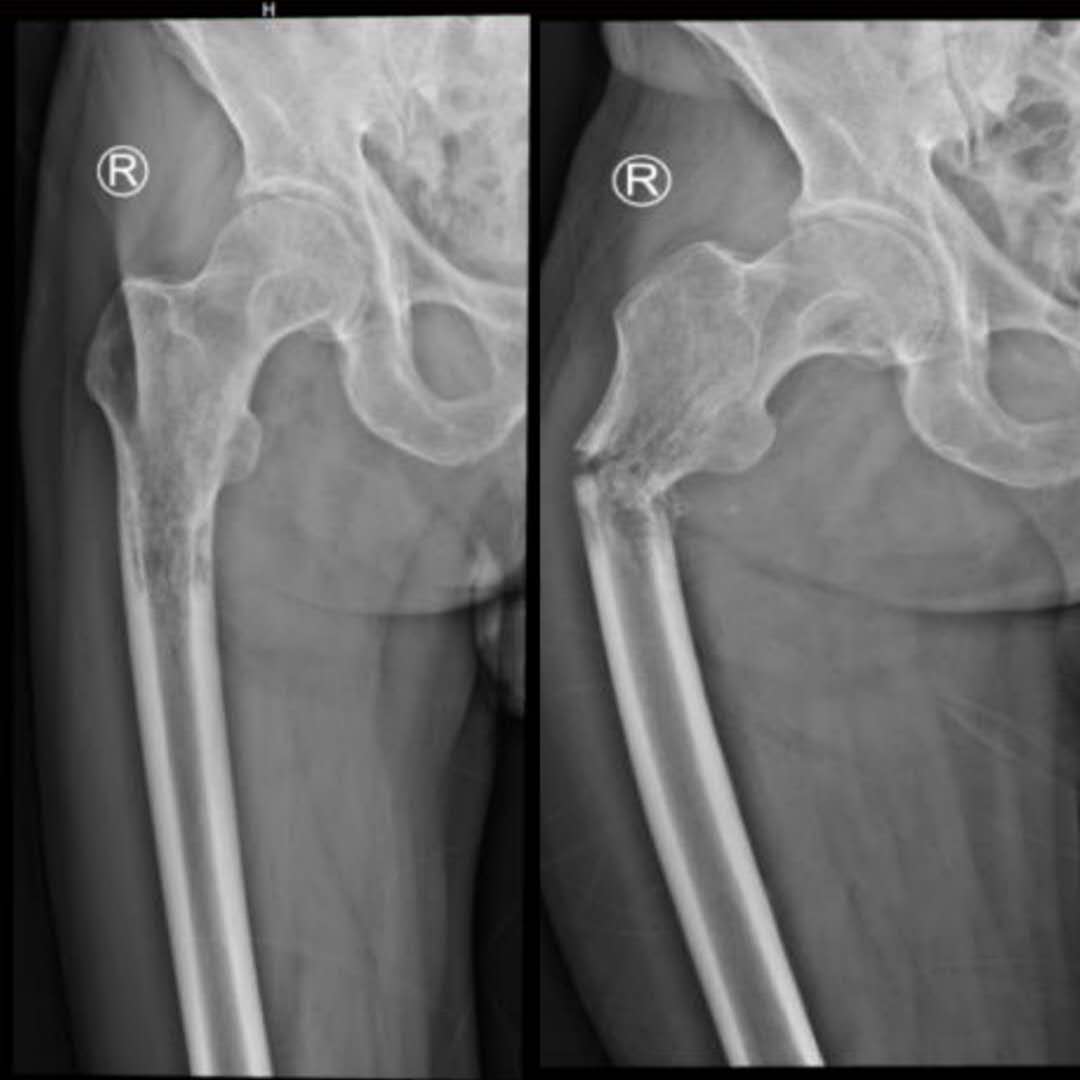

第二例患者男性,76岁,因“右大腿剧烈疼痛伴烦躁失眠,活动明显受限40余天”入院。查体见:痛苦病容,右大腿上端略肿胀,局部皮温略高,可触及包块,扣压痛明显,有骨擦音及异常活动,叩击足底时右大腿根部剧烈疼痛,余无明显异常。初步诊断为右股骨恶性肿瘤并病理性骨折。入院检查右股骨X线提示:右侧股骨近端虫蚀样骨质破,局部软组织密度改变。胸部CT平扫:1.双肺间质性改变,左肺上叶空洞型病变,邻近多发小结节及条索影,结核多考虑,请结合临床。 2.甲状腺多发钙化灶及小结节。 3.SPECT全身骨显像:右侧股骨近端代谢增高与减低并存,骨肿瘤与骨结核待进一别。穿刺活检病理提示为:(股骨)转移性腺癌。全身检查,未发现原发灶。该患者疼痛症状剧烈,伴烦躁不安,昼夜不眠,食欲不振,非常痛苦,服药效果不佳,曾要求截肢。其家属也强烈要求手术,全身严格评估后,术前多学科讨论认为符合手术适应症,遂顺利行瘤段切除,人工假体置换重建术,历时3小时半。术后患者以上不良症状均明显缓解,患者感激涕零,活动明显增加,三天后扶拐下地,医患双方对疗效非常满意,准备两至三周后行化疗及支持治疗。

术前X片图